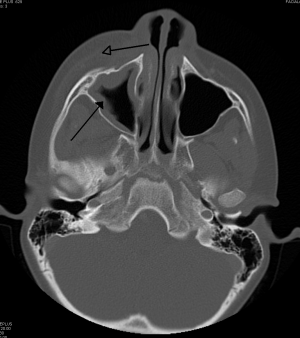

Periorbital cellulitis caused by a dental infection (also causing maxillary sinusitis).

- CT Orbit with IV contrast if:

- Concern for orbital cellulitis-i.e. equivocal assessment of proptosis, red eye, EOM function or pain w/ eye movement